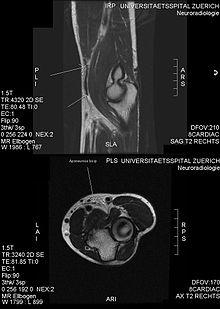

MRI: tear of the distal biceps tendon

Injuries could have occurred due to incorrect form, careless mistakes and ego lifting. The most common injury caused by biceps curls is biceps tendon tears.[32] There are two main causes of biceps tendon tears: heavyweight and overuse. Overuse is the result of ageing, and it also could be caused by exercise. But in most cases, it's the heavyweight that causes the injury.[33] For many beginners or even advance trainers can make a mistake known as "ego lifting",[34] which means the attempts to lift weights that are heavier than their capability to fulfill their ego. During an ego lifting, the form will be twisted because the weight is too heavy, and if the weight is far beyond their strength, then there is a likelihood to suffer from biceps tears. [35]